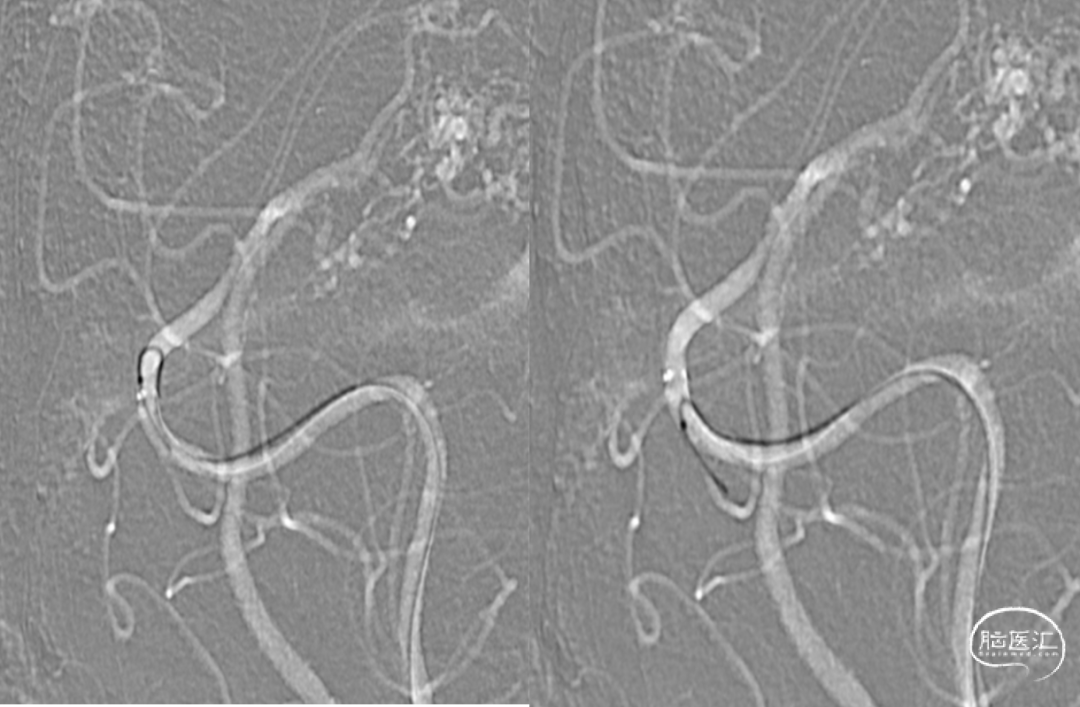

15%外科胶做塞子,注射Onyx18栓塞

静脉入路超选

供血动脉球囊保护;静脉压力锅技术,onyx18栓塞